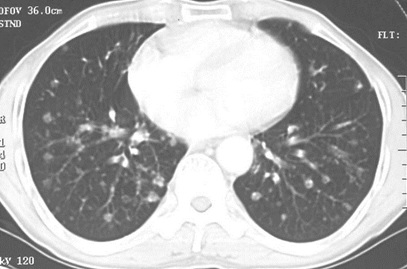

男性,55歲,結(jié)腸癌術(shù)后2年。(本題滿(mǎn)分2.00分)

結(jié)腸癌

A.大葉性肺炎

B.浸潤(rùn)性肺結(jié)核

C.原發(fā)性肺癌

D.肺轉(zhuǎn)移癌

本題答案:D

題目解析:【該題針對(duì)“CT-肺癌”知識(shí)點(diǎn)進(jìn)行考核】